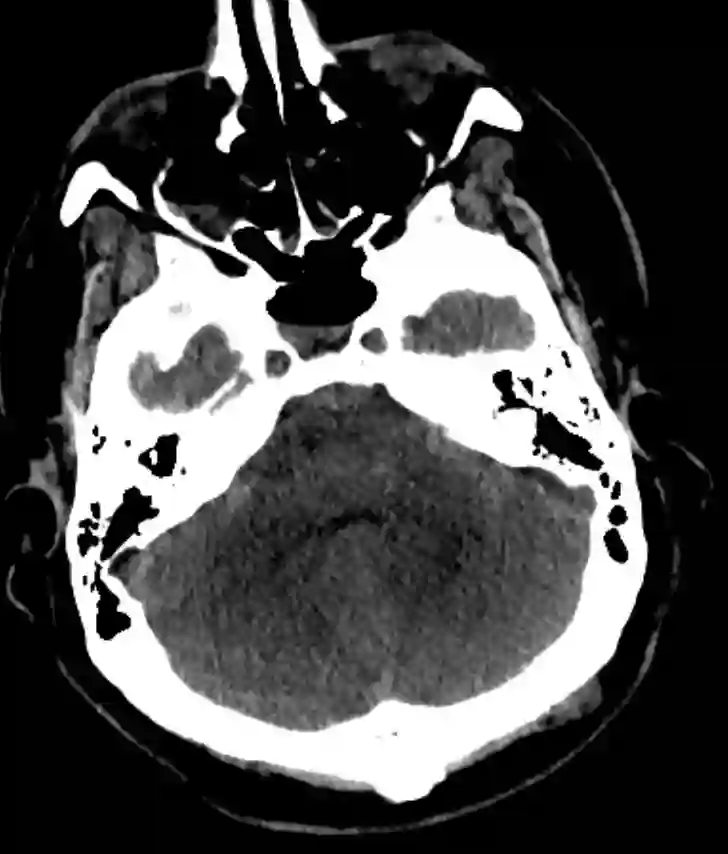

Axiales CT Bild mit einer kleinvolumigen Duret Blutung nach Schädelhirntrauma.

Duret Blutungen treten üblicherweise in der Mittellinie, paramedian und in den ventralen Regionen des Tegmentum, der oberen Pons und des Mesencephalons3 auf. Sind solche Blutungen bereits im CT initial nach dem Trauma sichtbar, gelten sie als prognostisch ungünstig für den weiteren Verlauf, einzelnen Fallberichten zufolge sind auch selten funktionell gute Erholungen beschrieben worden4.